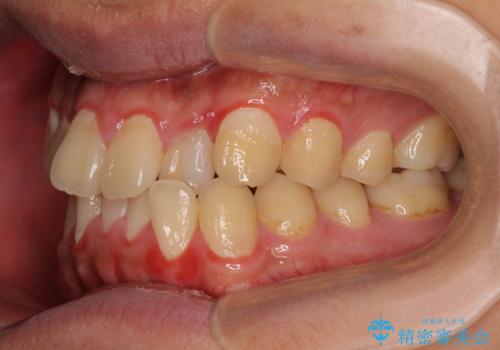

- 前歯のデコボコとクロスバイトを気にして来院された患者様です。

クロスバイトはありましたが、叢生の程度としては酷くなかったため、ワイヤー矯正でもマウスピース矯正でも、好きな方を選択していただきました。

治療開始前は汚れが多く、全体的に歯肉が腫れていましたが、矯正治療を通して腫れも少しずつ改善されました。